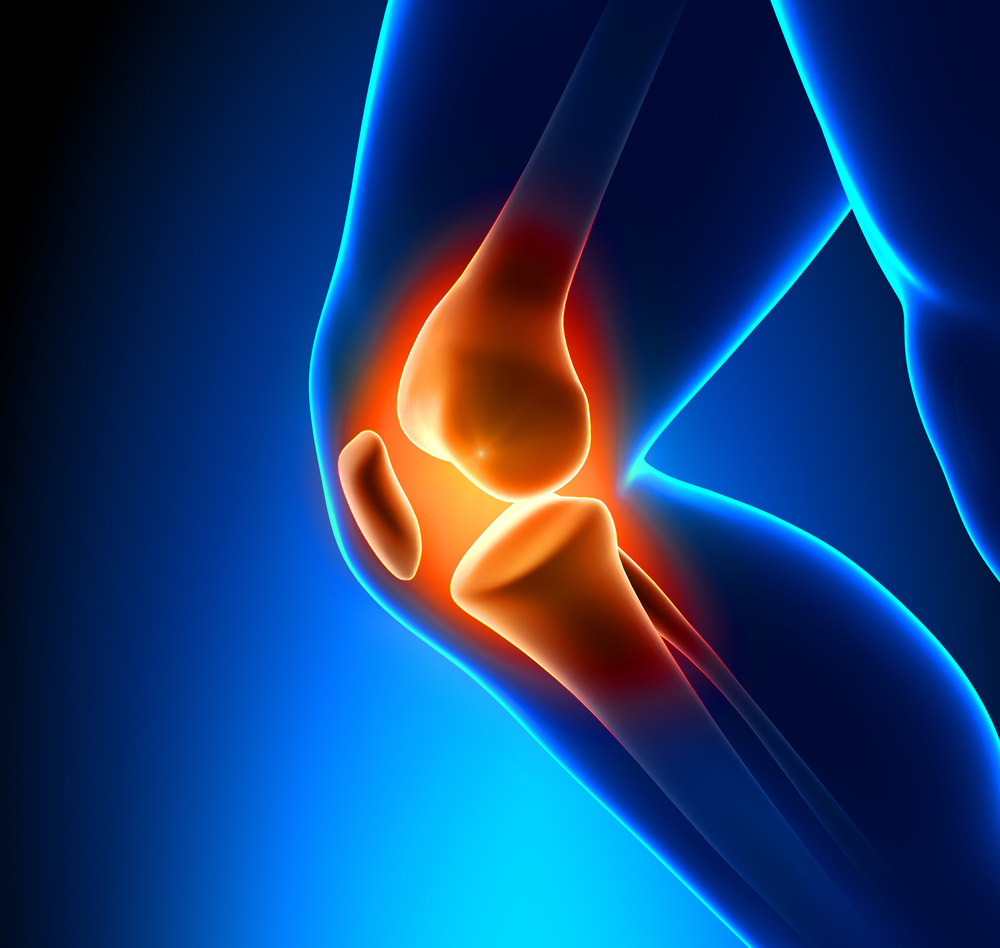

Joint Replacement

Rothman Orthopaedics' Joint Replacement Program is one of the nation's top joint replacement centers, performing more than 17,000 joint surgeries annually.

Because like all surgeries, joint replacement procedures do require some recovery time, they are normally only considered after all other non-surgical options have been discussed and/or attempted. Normally, joint surgery provides significant and wonderful results for the majority of patients. At Rothman Orthopaedic Institute, patients have the advantage of being seen by physicians who have actually helped develop and launch joint replacement techniques and who are considered to be well-renowned authorities on the topic of joint replacement

Is it right for you?

If you experience pain in any of your joints due to physical activities such as walking, running, and climbing stairs, it may be time to have a Rothman Orthopaedic Institute specialists diagnose your case. Joint replacement may be the answer for you. When simply sitting in a favorite chair or sleeping in your bed causes enough pain to wake you or make your life extremely uncomfortable, joint replacement may be able to get you back to an active lifestyle with less pain.